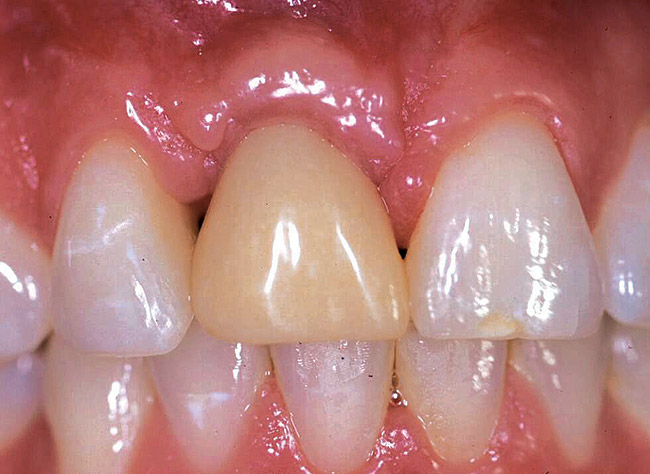

Fig 3. Preoperative image of tooth No. 8.

Figure 3